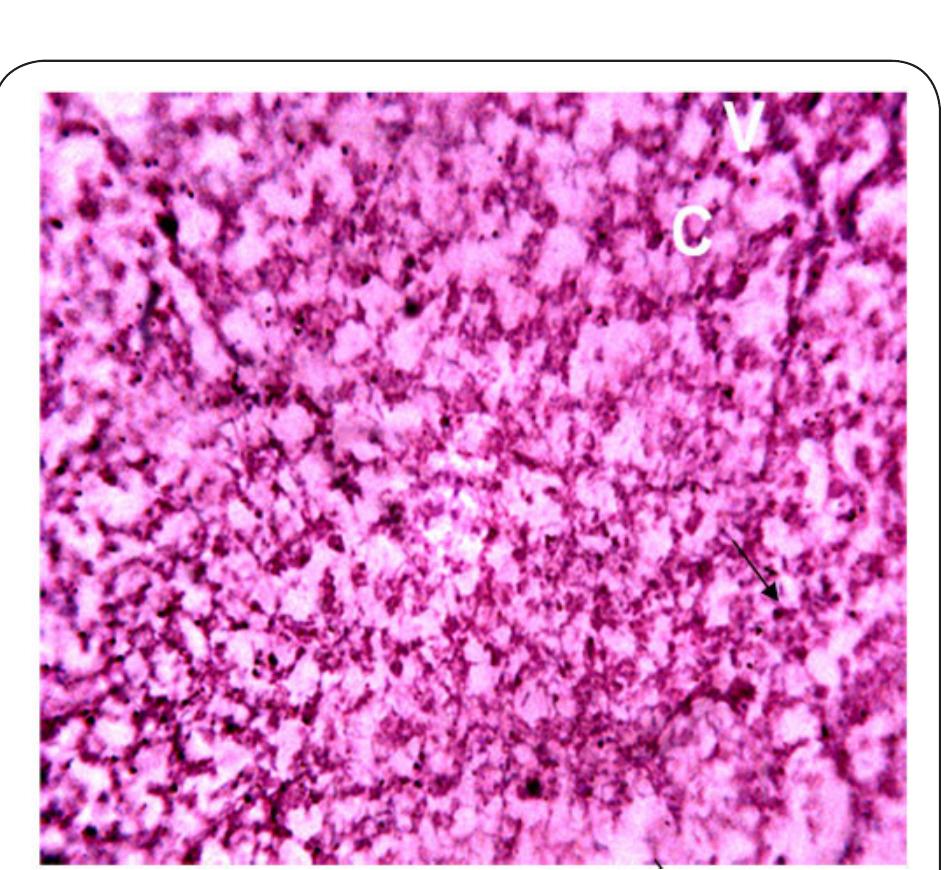

Dr. Ozovehe Patrick Samuel - FEDERAL UNIVERSITY OF TECHNOLOGY, MINNA-NIGERIA